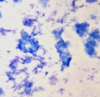

what inflammation is shown here

pyogranulomatous inflammation